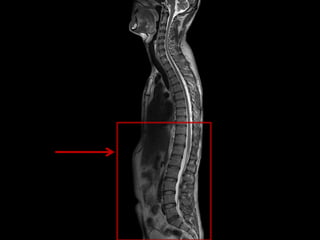

This document lists anatomical structures in the human abdomen including the umbilicus, aorta, skin, subcutaneous fat, sigmoid colon, erector spinae muscles, transverse colon, urinary bladder, right lobe of liver, gall bladder, and pancreas.